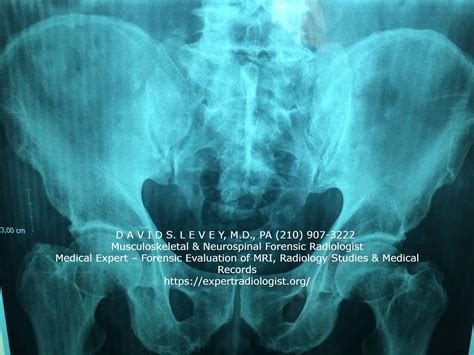

Hey guys, let’s dive into the world of medical imaging and explore what makes a Nelson Radiologist such a crucial part of healthcare. When we talk about Nelson Radiologist , we’re really talking about highly trained medical professionals who specialize in interpreting medical images like X-rays, CT scans, MRIs, and ultrasounds. These images are like a secret code that helps doctors diagnose diseases, monitor treatment progress, and even guide minimally invasive procedures. The accuracy and insight provided by a skilled radiologist can quite literally be the difference between life and death, or at least a significant impact on the quality of life for a patient. Think about it: a subtle shadow on an X-ray, a tiny anomaly on an MRI – these are the things that a radiologist, with their trained eyes and deep understanding of anatomy and pathology, can spot when others might miss them. They are the detectives of the medical world, piecing together clues from these visual representations to paint a clear picture for the patient’s treating physician. The field of radiology itself is constantly evolving, with new technologies and techniques emerging all the time. This means that a Nelson Radiologist isn’t just looking at static images; they are often working with cutting-edge equipment that provides incredibly detailed views of the human body. This allows for earlier and more accurate diagnoses, which in turn leads to more effective treatment plans. It’s a demanding field, requiring years of rigorous education and continuous learning to stay at the forefront of medical advancements. We’re talking about medical school, followed by a demanding residency program in radiology, and often further subspecialty fellowship training. This dedication ensures that when you need a radiologist, you’re getting someone with unparalleled expertise in their field. The role of a radiologist extends beyond just reading scans; they often collaborate closely with other physicians, discussing complex cases and offering their expert opinions to ensure the best possible patient care. They are integral members of the healthcare team, contributing vital information that guides surgical decisions, chemotherapy regimens, and follow-up care. Their work is often behind the scenes, but its impact is profound, touching the lives of countless individuals every single day. Understanding the importance of a Nelson Radiologist means appreciating the intricate science and dedicated skill involved in medical imaging and diagnosis.

When it comes to getting to the bottom of what’s ailing you, the expertise of a Nelson Radiologist is absolutely paramount. Guys, imagine you’ve had a scan – maybe it’s an MRI for a knee injury or a CT scan to check for something more serious. That scan generates a ton of data, a complex series of images that require a special kind of vision to interpret. This is where our Nelson Radiologist shines. They possess a unique understanding of human anatomy, physiology, and the myriad ways diseases can manifest visually within the body. It’s not just about seeing something; it’s about understanding what that ‘something’ means in the context of your symptoms and medical history. They can differentiate between a normal anatomical variation and a sign of pathology, which is a huge deal. For instance, a radiologist might identify a small nodule on a lung CT scan. While it might seem insignificant to the untrained eye, a radiologist will assess its size, shape, density, and location, comparing it to previous scans if available, to determine if it’s something to be concerned about – perhaps an early sign of cancer that requires further investigation. This Nelson Radiologist is essentially the translator between the complex visual language of medical imaging and the practical needs of diagnosis and treatment. They write detailed reports that explain their findings in clear, concise terms, allowing your primary care physician or specialist to make informed decisions. Without this critical interpretation, those scans would just be a collection of pictures, offering little diagnostic value. Think about the sheer volume of information a radiologist processes. They often review hundreds of images a day, each requiring careful attention and critical analysis. This level of dedication and precision is what makes their contribution so invaluable. Furthermore, radiologists are not just passive interpreters. Many are involved in interventional radiology, a subspecialty where they use imaging guidance to perform minimally invasive procedures. This could involve draining an abscess, placing a stent, or performing a biopsy – all while using real-time imaging to navigate the body with incredible accuracy. So, when you hear about a Nelson Radiologist , understand that you’re talking about a cornerstone of modern medical diagnostics, a professional whose keen eye and specialized knowledge are essential for your health journey. They are the unsung heroes who help uncover the hidden truths within your body, paving the way for effective treatment and recovery. Their role is truly indispensable in providing comprehensive and high-quality patient care.

Okay guys, let’s get real about the incredible technology that a Nelson Radiologist uses every single day. It’s not like the old days of just black and white X-rays, though those are still super important! Modern radiology involves some seriously advanced gear. We’re talking about MRI machines that use powerful magnetic fields and radio waves to create highly detailed images of soft tissues – think brains, muscles, and ligaments. Then there are CT scanners , which use X-rays from multiple angles to build cross-sectional images, giving us a fantastic view of bones, organs, and blood vessels. Ultrasound uses sound waves to create real-time images, which is awesome for looking at things like a developing fetus or the flow of blood. And let’s not forget about PET scans , which can show us metabolic activity in the body, helping to detect cancer or assess heart conditions. What’s really cool is how a Nelson Radiologist doesn’t just operate this equipment; they understand the physics and biology behind it all. They know how to optimize the settings on an MRI to get the best possible view of a specific area, or how to adjust the contrast on a CT scan to highlight certain structures. This technical mastery is crucial because the quality of the images directly impacts the accuracy of the diagnosis. Think about it: if the image isn’t clear, or if the right type of scan isn’t used, subtle abnormalities can be missed. A Nelson Radiologist is trained to select the most appropriate imaging modality for a particular clinical question and to perform or supervise the acquisition of high-quality images. They also work with contrast agents , substances that are injected or swallowed to make certain tissues or blood vessels show up more clearly on scans. Choosing the right contrast agent and knowing how to administer it safely is another key skill. Beyond just the hardware, there’s also sophisticated imaging software that allows radiologists to manipulate the images, create 3D reconstructions, and even perform quantitative analysis. This digital revolution in radiology means that a Nelson Radiologist is often working with advanced workstations, where they can zoom in, measure structures, and compare images over time with incredible precision. The integration of artificial intelligence (AI) is also becoming a huge part of radiology, with AI algorithms helping to detect potential abnormalities or prioritize urgent cases. A Nelson Radiologist is at the forefront of understanding and utilizing these new tools to enhance diagnostic accuracy and efficiency. It’s a field that demands continuous learning, as new technologies and techniques are always emerging. So, the next time you hear about a radiology scan, remember the complex technology and the highly skilled professional, the Nelson Radiologist , who is making sense of it all for your health.